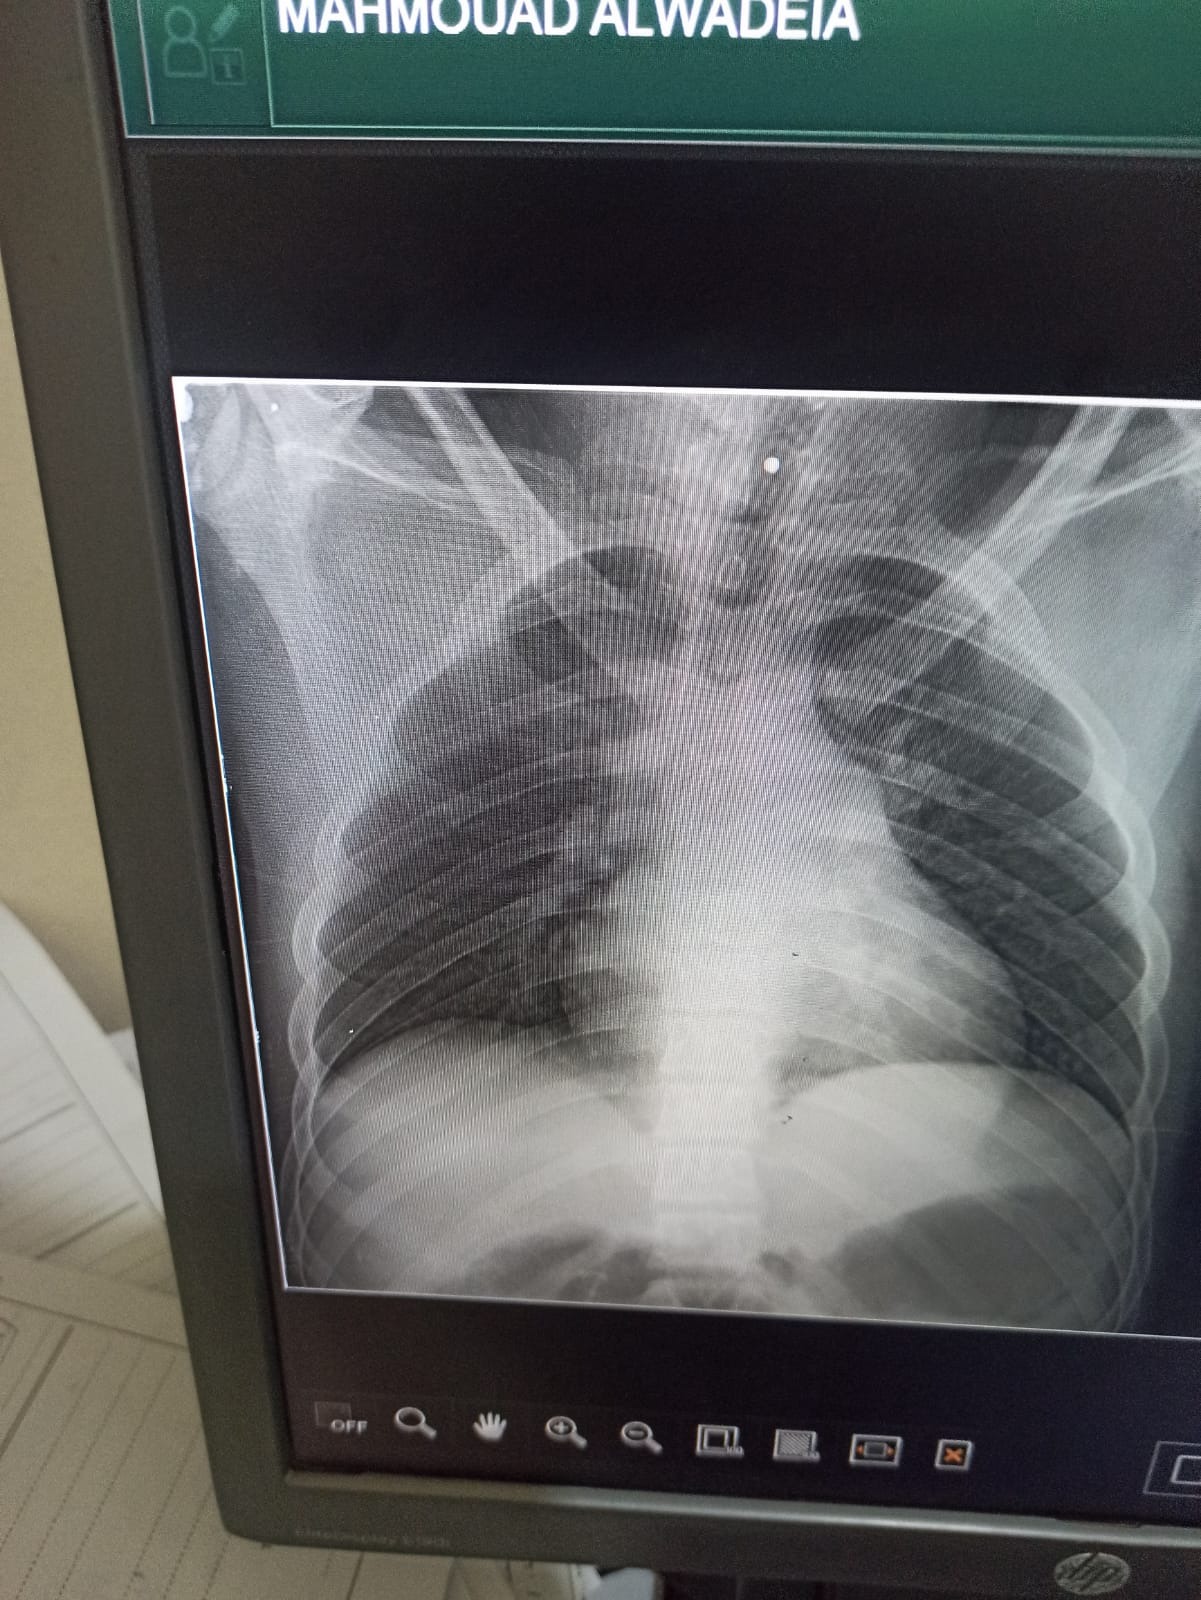

As I walked home, an Israeli artillery shell struck the street. In a split second, everything went dark. I was hit by shrapnel in the head, neck, and throughout my body. A shard of metal lodged in my cervical spine specifically the seventh vertebra leaving me paralyzed. I now suffer from quadriplegia. My arms, my legs… nothing moves.